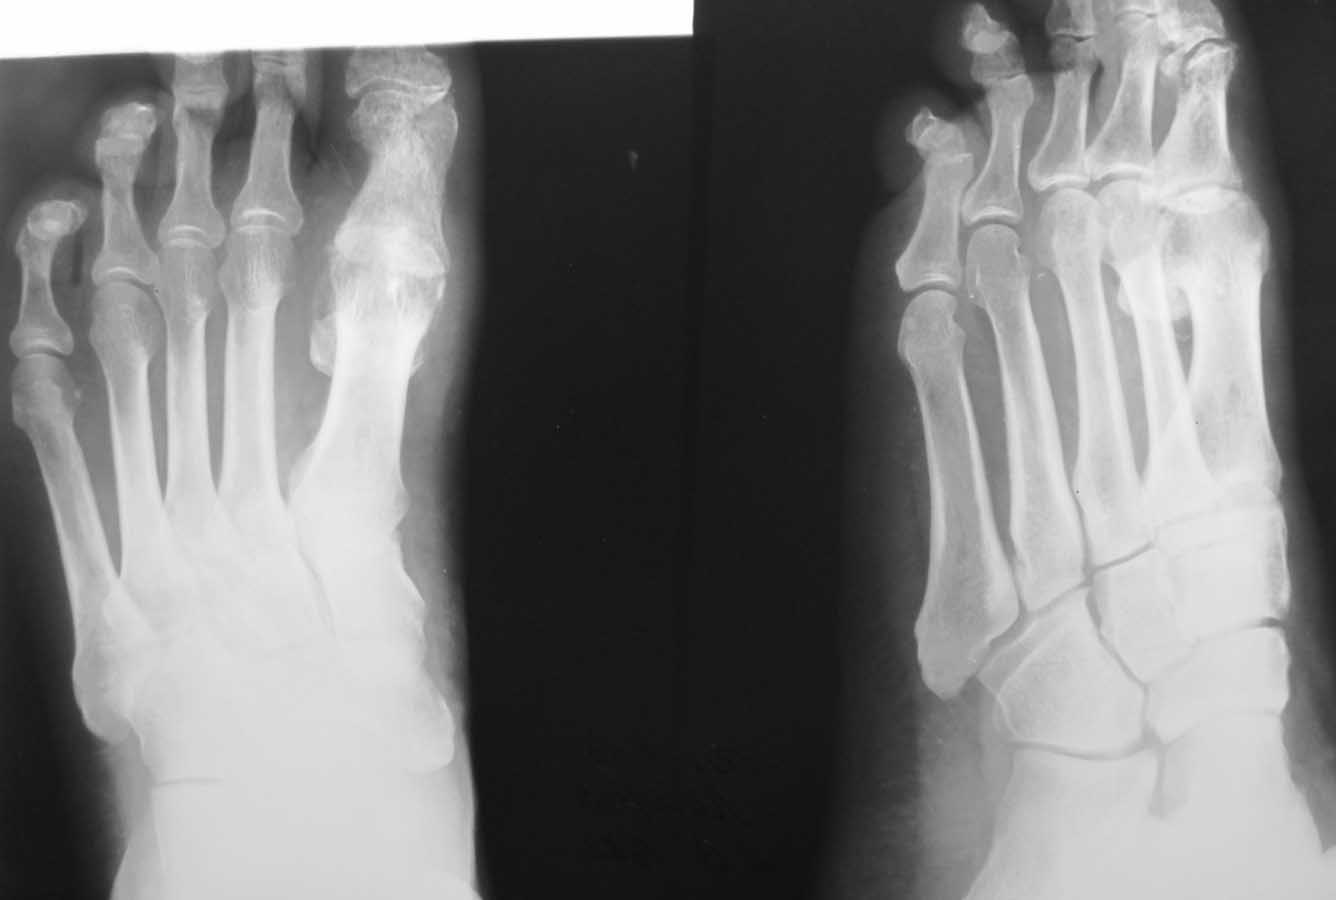

Здравствуйте, коллеги. Помогите с тактикой дальнейшего лечения.Мужчина 52 года, активный

физически. В марте 2012 оперирован по поводу ДОА плюсне-фалангового сустава 1 пальца,

сделана резекция основания основной фаланги и остеофитов головки плюсневой кости.

Послеоперационное лечение: массаж, физиотерапия. В настоящее время беспокоят сильные

боли в суставе, сохраняется ограничение движений. Дальнейшая тактика: артродез ПФС?,

Эндопротезирование ПФС?, повторная резекция основной фаланги? Мнения наших коллег

разделились. На фотографиях: вид стопы в настоящее время, рентгенограммы до операции,

после операции, в настоящее время. Прошу прощения за неважное качество снимков.